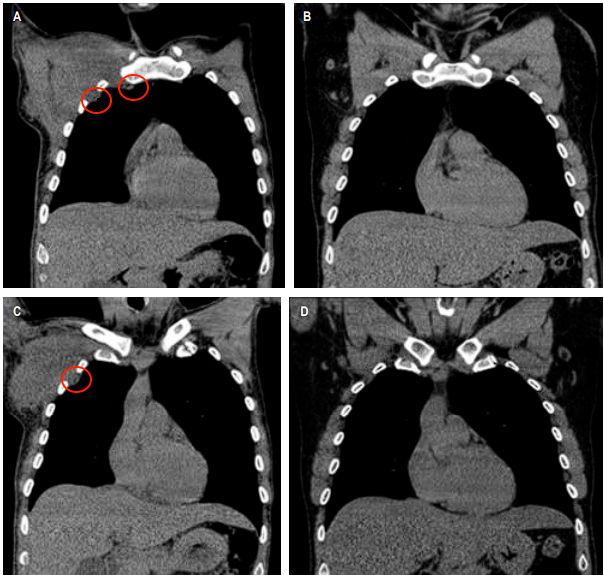

其次,人体最高的耐受热约为40.6~41.4摄氏度。如果发烧达到42摄氏度(家庭常用的体温计上限是42摄氏度,因为一般的发烧很难达到这个温度,即使达到了,人体大脑和内脏也很难承受超过42℃的高烧),即便高烧持续时间很短,也极有可能会导致永久性脑损伤、发生心肺功能衰竭,并有死亡风险[2]。总的来说,用发烧的方法来“杀死”癌细胞是不可行的!严重高烧可是会马上危胁生命的,而肿瘤是慢性病,并不会马上致命,结果可能是——肿瘤细胞没死,人也消耗得差不多了。又有患者疑问:“发烧不能杀死肿瘤,但我听说感染新冠后让肿瘤消失,这是真的吗?”当听到新冠会让肿瘤消失这件事,科普君的第一反应和大家一样:不相信,肯定是谣言。但事实上,感染新冠后,肿瘤奇迹“消失”还真有真实的临床案例,不是谣言。案例1:霍奇金淋巴瘤患者感染新冠病毒后,体内肿瘤几乎消失殆尽![3]2021年1月2日《英国血液病杂志》报道了一则医学奇迹:一名被诊断为霍奇金淋巴瘤、同时还患有严重肾功能衰竭、感染了EBV病毒的患者,被确诊感染了新冠病毒后,经过治疗,患者的新冠抗体转阴性后出院回到家中修养。这期间他没有用任何药物进行抗肿瘤治疗,但神奇的事,四个月后这名患者去医院做癌症常规检查时却发现,其体内大部分肿瘤竟神奇消失了。左边的图像中的黑色区域显示患者体内各处还散布着可怕的癌细胞;右边图像则显示肿瘤几乎完全消失案例2:纤维结缔组织瘤患者感染新冠后,胸部肿瘤奇迹消失[4]一位患者有艾滋病,同时还被断为纤维结缔组织瘤的患者,原本计划手术切除肿瘤,但手术前他感染了新冠病毒,不得不推迟手术,并使用对乙酰氨基酚和甲泼尼龙对症治疗。1个月后,医生通过触诊和CT检查却发现,患者胸部原有的肿块消失了!居然有这种好事!不是说癌症患者感染新冠会更危险吗?如果感染新冠病毒真能杀死癌细胞,让肿瘤消失,是不是可以主动感染新冠,那样说不定肿瘤消失这种好事就能降临降到自己身上呢。某些癌症患者感染新冠后肿瘤“不治而愈”,很可能是患者的免疫系统被再次“激活”,在对付新冠病毒的同时,“杀疯”了的免疫系统连体内的肿瘤细胞也顺手给灭了,算是一个偶然的意外收获,但这种情况可遇不可求。肿瘤患者普遍免疫力较低,部分患者还患有基础病,因此感染新冠后转重症的风险也会高于普通人。如果感染后不积极处理,后果可能会非常严重。例如,对于放化疗、靶向治疗期间的患者,由于这些治疗手段会抑制免疫,免疫清除能力低,感染新冠后可能会引起继发感染,癌细胞也更容易繁殖和扩散,有可能导致重症的发生。即使是已经处于康复期的患者,如果听信了“感染新冠能抗癌”,而不及时接受对症治疗,无疑给了癌细胞壮大的机会,导致癌细胞有机会不断地发展壮大,最终变成癌细胞转移扩散[5]。总而言之,个别肿瘤患者感染新冠后癌细胞奇迹消退,这是极低概率的事,并不是每个人都拥有这种“超能力”。因此,不建议肿瘤患者为了抗癌,而故意去感染新冠病毒。无论是“感染新冠病毒后发高烧可以消灭癌细胞”,还是“感染新冠病毒可以让肿瘤消失”,在这里互助君再次提醒:发烧不能烧死癌细胞,“阳了”建议要及时退烧。目前得新冠能不能让肿瘤消失还有待考证,个别肿瘤患者感染新冠后肿瘤神奇好转只是特殊个案!万不可仿效!感染新冠,肿瘤患者重症率和死亡风险都比一般人高,所以更应该:严格做好个人防护,尽力避免感染新冠。一旦感染新冠病毒后更应该:及时对症治疗,不要心存侥幸。对于不幸“阳了”的肿瘤患者,不要慌,根据国内数据结果发现,约80%新冠肺炎患者表现为轻症(轻型、普通型),预后良好[6]。因此感染后建议先判断一下自己是轻症还是重症。轻症:发热、咳嗽、咽喉痛、头痛、味觉及嗅觉丧失,但无明显气短、呼吸困难或胸部影像学异常。一般建议居家对症处理,多休息,适度多饮水。必要时(有发烧情况)咨询主治医生,在医生的指导下服用治疗药物。重症:持续发烧3天以上,而且出现心率增快、咳嗽咳痰加重、呼吸困难、口唇发干等表现,不要犹豫,立即就医。根据《美国国家癌症综合网络(NCCN)癌症相关感染的预防和治疗指南2022.3版》建议:新冠病毒检测阳性的肿瘤患者,建议推迟抗肿瘤治疗。